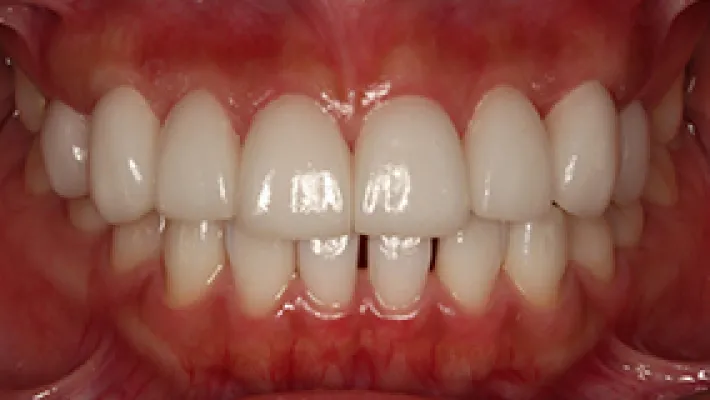

上前歯8本 ラミネートベニア

施術前

施術後

削らないラミネートベニアと歯肉整形ですきっ歯・歯並び・歯の形を改善した症例です。全体的にホワイトニングをしてから、歯肉整形と削らないラミネートベニア8本を行いました。

*ラミネートベニアは削って被せるセラミッククラウンに比べると強度や耐久性は劣ります。この症例でもラミネートベニアは支台の歯を削っていません。

*削らないラミネートベニアは削らないで接着するため、元の歯よりも厚く大きくなります。